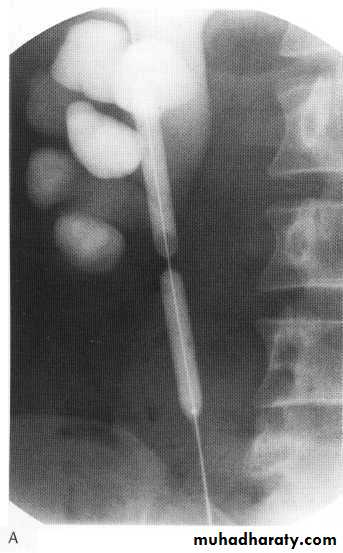

Ivu FINDING OF ACUTE OBSTRUCTION

Increasingly dense ‘obstructive’ nephrogramModest kidney enlargement (50% of patients)

Delayed caliceal opacification

PCS and uretric dilation (g.1 mild PCS dilation ,g.2 moderate PCS dilation (blunting calyces),g.3 sever dilatation within thinning of parenchyma .

Spontaneous pyelosinus extravasations (up to 24% of patients